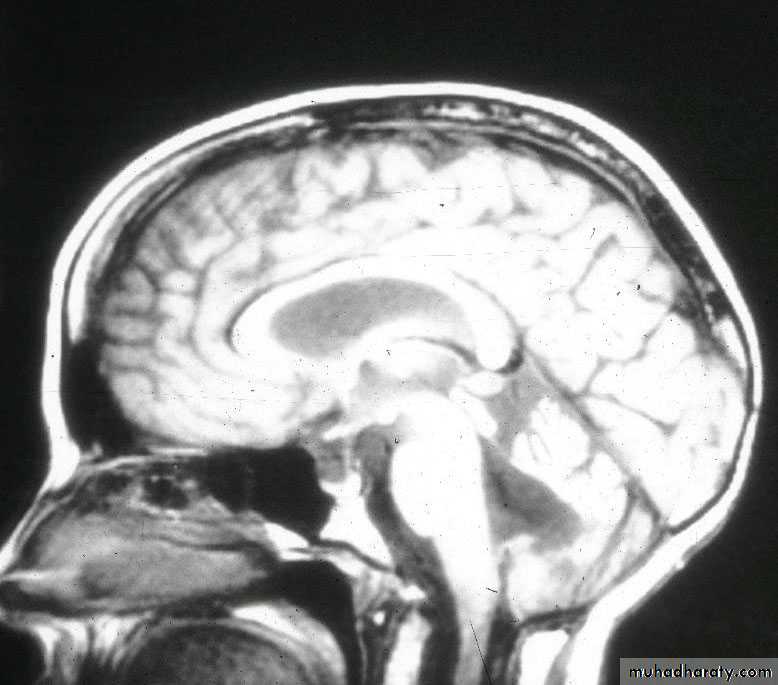

METASTATIC BRAIN TUMORS SAGGITAL MRI